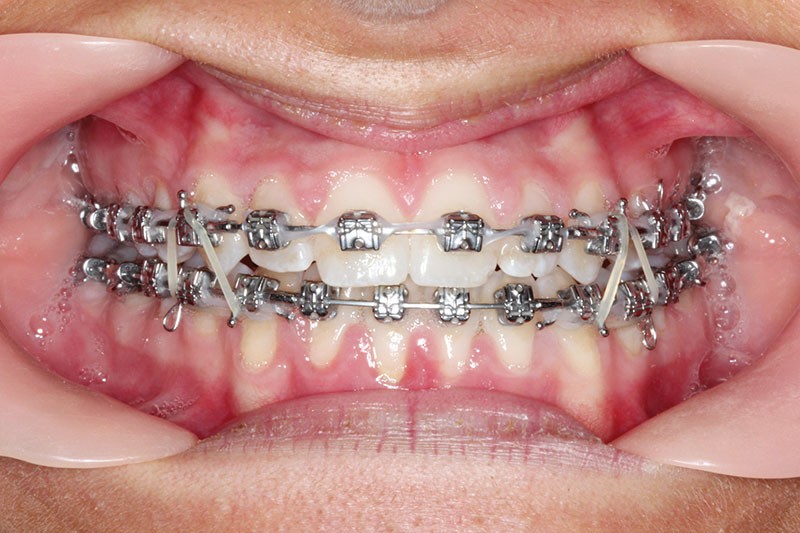

2e phase : mise en place du système multibague Carriere SLX (fig. 7 à 9)

Nous continuons le port des élastiques…